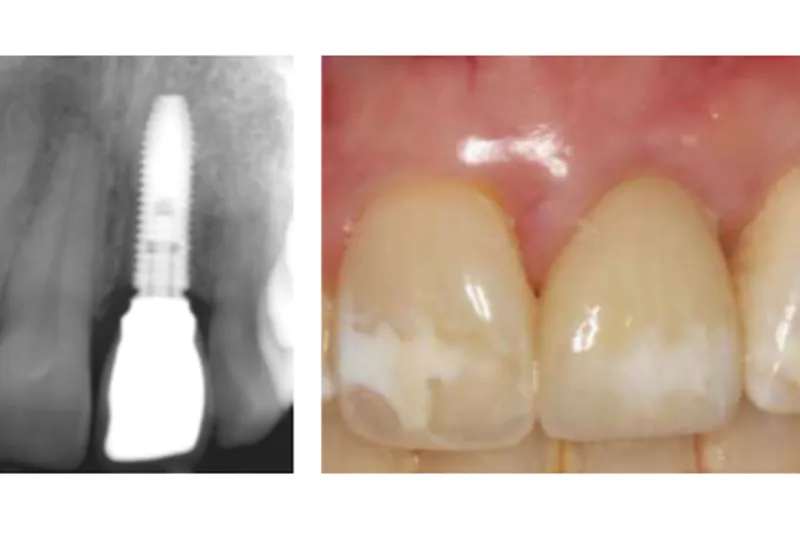

Desuden tyder det også på, at bevarelse af en endodontisk behandlet tand i forhold til ekstraktion og indsættelse af et implantat i det mindste på kort sigt resulterede i den bedste blødtvævsæstetik.